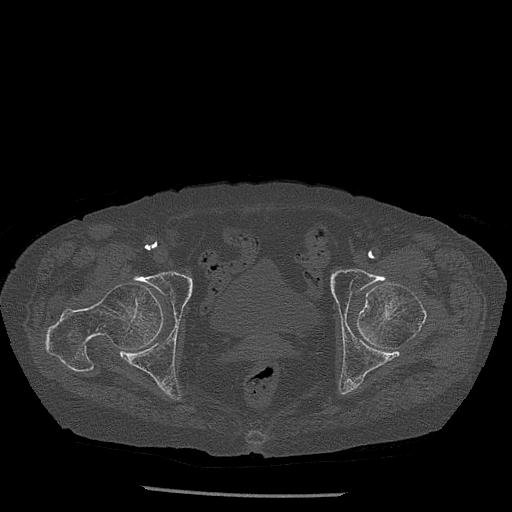

110286 2/17 股関節 2R 74歳女性 右人工骨頭